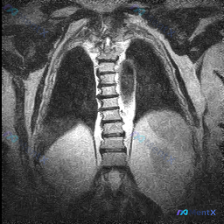

影像报「胸椎形态基本规整对称」,但高度怀疑脊柱侧弯?问题可能出在哪?

整理到一个有点矛盾的影像临床对照资料,想跟大家讨论下思路: 背景是临床高度关注「脊柱侧弯」的问题,但拿到的单幅胸部MRI冠状位报告是这么写的: - 胸椎序列在可视范围内形态基本规整 - 两侧肋骨形态对称,纵隔居中 - 未见明显椎体骨质破坏或压缩骨折 - 肺野、胸膜、纵隔、膈肌也都没报明显异常 简单说...